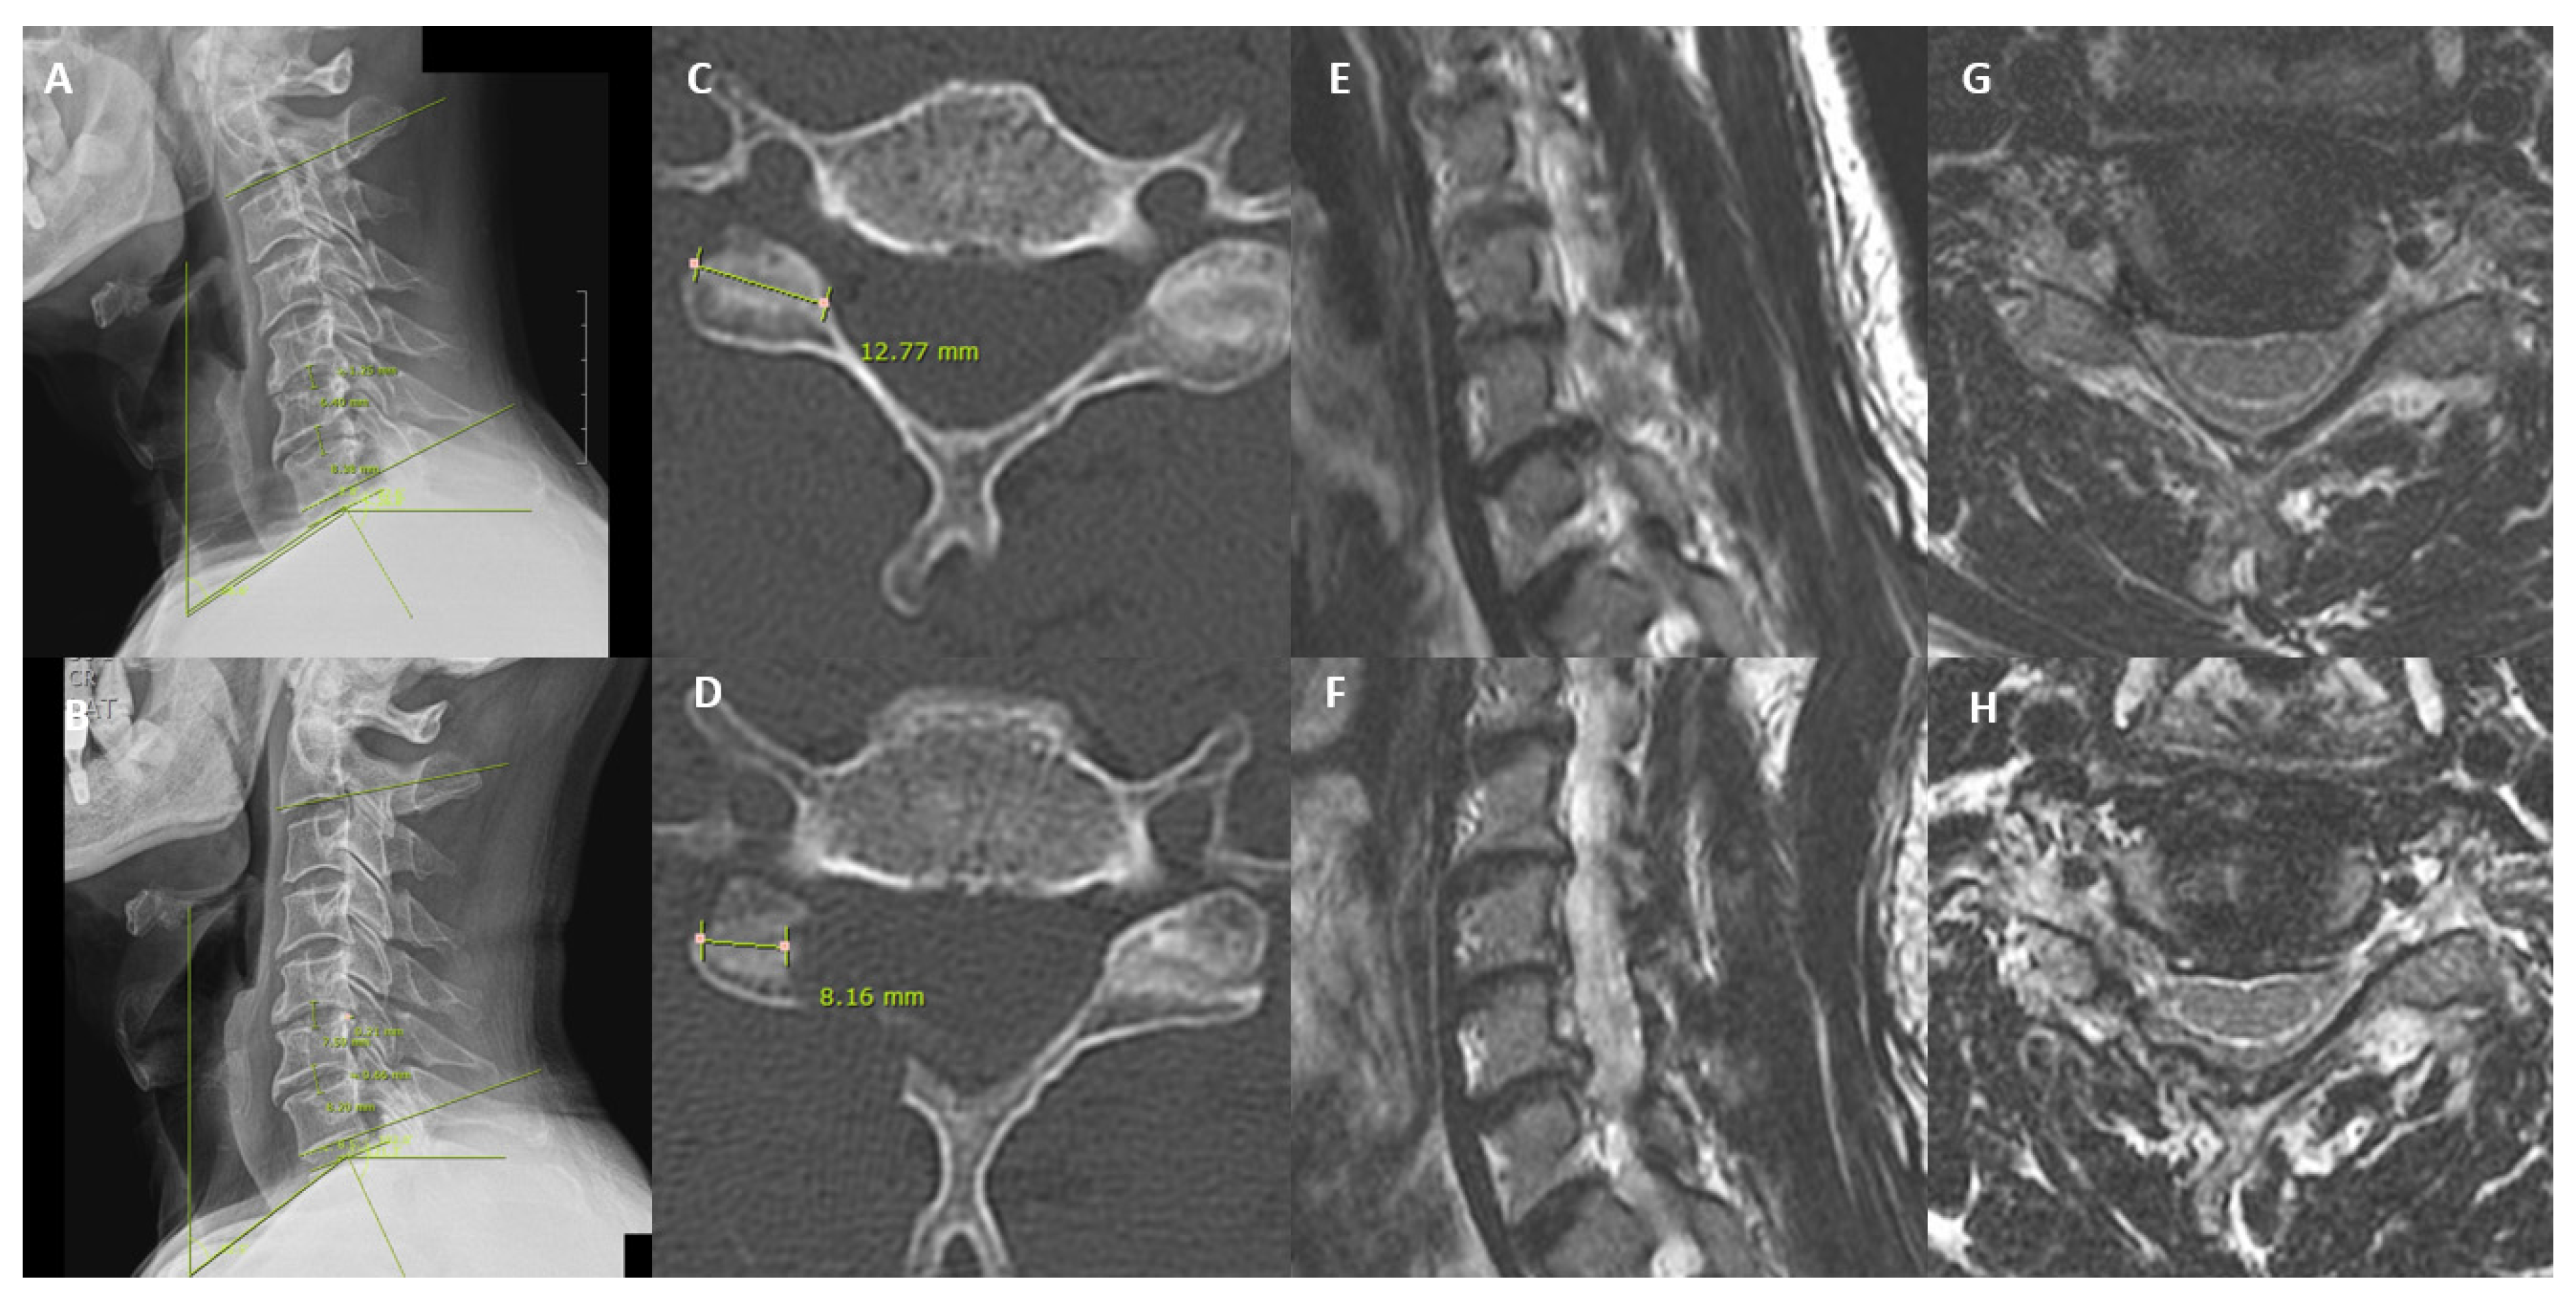

| C2–C7 angle at neutral (°) | |||||

| Preoperative | 5.08 ± 9.20 | - | 8.54 ± 11.42 | - | - |

| Postoperative | 9.24 ± 9.61 | 0.049 * | 8.85 ± 9.67 | 0.833 | 0.085 |

| Neck tilt angle (°) | |||||

| Preoperative | 55.05 ± 7.22 | - | 52 ± 9.71 | - | - |

| Postoperative | 43.37 ± 17.79 | <0.001 * | 53.35 ± 8.05 | 0.271 | <0.001 * |

| T1 slope angle (°) | |||||

| Preoperative | 32.23 ± 17.60 | - | 23.92 ± 6.71 | - | - |

| Postoperative | 20.54 ± 6.50 | <0.001 * | 25.54 ± 7.02 | 0.148 | 0.002 * |

| Thoracic inlet angle (°) | |||||

| Preoperative | 75.65 ± 7.38 | - | 75.92 ± 10.86 | - | - |

| Postoperative | 75.90 ± 6.83 | 0.447 | 78.89 ± 9.05 | 0.079 | 0.111 |